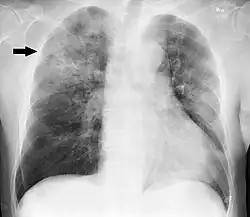

Clinical features of a respiratory tract infection may include initial symptoms of an upper respiratory tract infection mimicking a viral infection, usually associated with low-grade fevers. This may progress to the lower respiratory tract within a few days, with features often resembling those of wheezy bronchitis. Sputum may be difficult to expectorate and is often grey or creamy in color. The cough may persist for weeks without appropriate treatment. Many cases are diagnosed after presenting chest infections that do not respond to penicillins or first-generation cephalosporins. A chest X-ray can identify alveolar consolidation.[36]

H. influenzae can cause respiratory tract infections including pneumonia, otitis media, epiglottitis (swelling in the throat), eye infections and bloodstream infection, meningitis. It can also cause cellulitis (skin infection) and infectious arthritis (inflammation of the joint).[49]

Due to routine use of the Hib vaccine in the U.S. since 1990, the incidence of invasive Hib disease has decreased to 1.3/100,000 in children.[51] However, Hib remains a major cause of lower respiratory tract infections in infants and children in developing countries where the vaccine is not widely used. Unencapsulated H. influenzae strains are unaffected by the Hib vaccine and cause ear infections (otitis media), eye infections (conjunctivitis), and sinusitis in children, and are associated with pneumonia.[51]